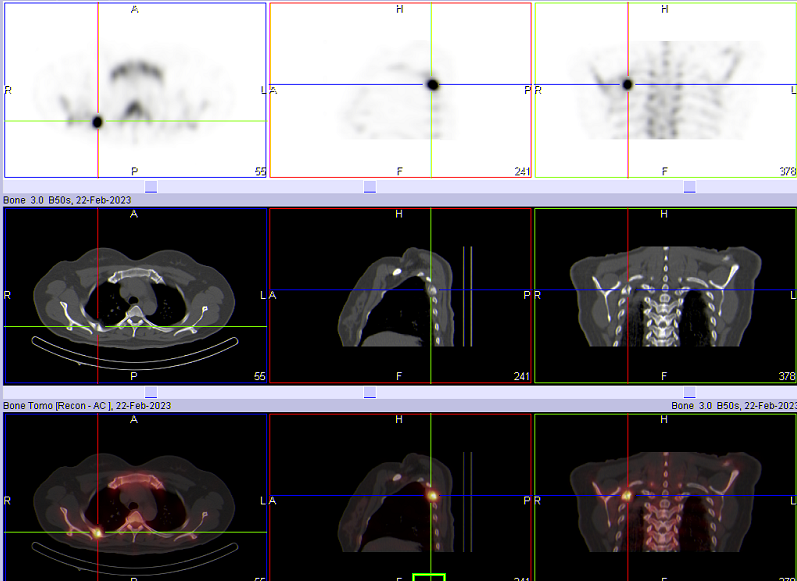

如图所示,胃恶性肿瘤患者,全身骨扫描显示:右侧第6腋肋放射性摄取增高,左侧第3-6前肋放射性摄取增高。进一步加做胸廓断层显像(SPECT/CT)后,影像显示右侧第6腋肋局部放射性摄取增高灶,肋骨骨密度增高,诊断为骨转移;左侧第3-6前肋放射性摄取增高,局部骨皮质皱褶,欠连续,诊断为陈旧性骨折。